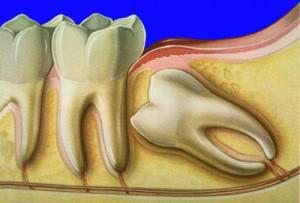

Ретинированным зубом мудрости называют своего рода аномалию зуба, располагающегося на 8 месте в ряду, а также являющегося третьим по счету моляром (большой коренной зуб). Суть данной аномалии заключается в том, что зуб мудрости не может прорезаться и занять отведенное для него место в челюсти. Вследствие этого зуб мудрости остается внутри кости или же немного прикрыт слизистой.

Причины возникновения ретинированных зубов могут быть разнообразными, но по статистике чаще всего ретенция зуба возникает вследствие раннего удаления молочных зубов в детстве или по причине неправильного расположения зубного ряда в челюсти, когда для прорезывающегося зуба просто нет места.